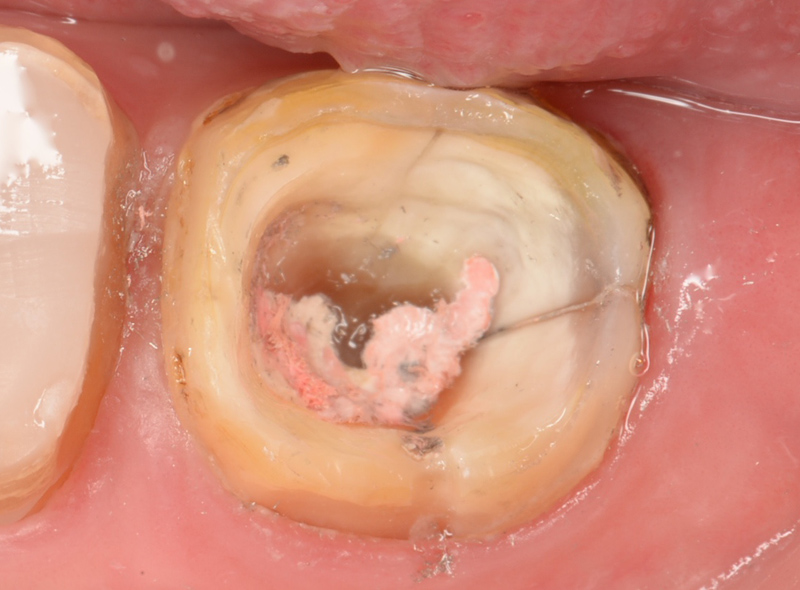

マイクロスコープとは歯科用顕微鏡ともいわれるもので、「肉眼」よりも数十倍(最大80倍)視野を拡大してくれる装置です。つまり肉眼では確認できない部位までを見ることができます。

下の画像は肉眼とマイクロスコープの見え方の違いです。

これだけの違いがあります。

目に見えない小さいものを見えるようにして行う治療と指の感覚でなんとなく行う治療ではどちらが正確で精密な治療が行えるかは一目瞭然かと思います。

多くの方が、原因が分からないまま、何回も根管治療されています。現実的に、肉眼での治療を続けている限り、根本的な原因が分かりませんので、その苦しみから解放される可能性は低く、最終的には抜歯の可能性が高まります。可能であれば早い段階で、マイクロスコープによる精密治療をお勧めします。